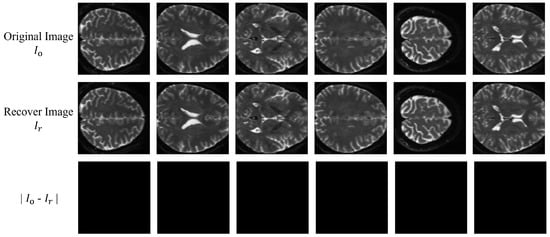

Table 2 shows the average BER values of the extracted watermark and the average PSNR values of the recovered image and the cover image for 64 slice images under the no-attack condition. Figure 12 displays the visual results of the differences between six slice images and their corresponding recovered images. It can be seen that the average BER value of our proposed algorithm is 0, and the average PSNR value is 1, indicating that our proposed algorithm can extract the watermark information and recover the cover image losslessly under no attack.

Figure 12.

Visualization results of the recovered images of six slice images.